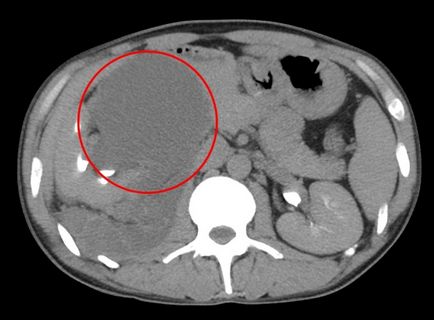

egy nagy tumor

Photo ciszták a vesében, a fent hivatkozott, azt mutatja, hogy a patológia végül nőnek a hatalmas mérete. Ebben az esetben, az hatással van a nagy területen test felületén okoz veseelégtelenséget és sok mellékhatással betegség.

Figyelembe véve a ciszták a vese fenti képen látható egy nagy szürke folt. Ez a hely a kijelző egy nagy cisztás test, csatlakozik a test szöveteiben.

Daganatok a nagyméretű

Úgy néz ki, mint egy ciszta ultrahangra fenti képen látható összes részletet. Általában ciszták a képek jelennek meg egy közepes vagy nagy méretű foltok vagy eszméletvesztést néhány ág vagy csatornákat.

a tumor mérete

Attól függően, hogy a színpad és elhanyagolása ciszták, a mérete változhat 3-4 cm-ig 15-17 cm vagy több.